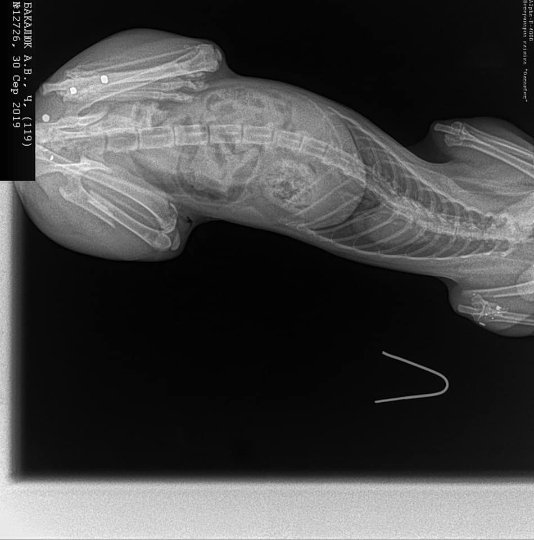

Неподалік Луцька невідомі стріляли у кота. ФОТО 18+

У селі Озерце невідомі кілька разів поцілили у кота.

Окрім того, автор допису оприлюднив фотографії кота після хіхругічного втручання і написав, що тварині потрібно зробити ще дві операції.